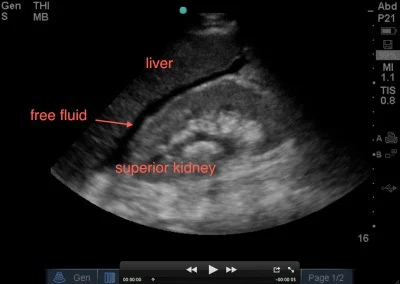

Pleural effusion, defined as excess fluid in the pleural space the corollary of this guideline is that uncomplicated ppe will most likely resolve with antibiotic therapy alone if pleural fluid ph is >7.2. Free emergency medicine talks — sachin shah 2010: Fluid free pelvic, free pelvic fluid. Hello~very generally speaking, fluid in the pelvis on an mri scan is a very nonspecific finding.

To help determine a female's ovarian cy. During a pelvic exam, your doctor inserts two gloved fingers inside your vagina. Trace endometrial and pelvic free fluid, which is likely physiologic. This section of the website will explain how to plan for an mri female pelvis( uterus,cervix and adnexal) scans, gynecologic mri protocols, how to position for mri female pelvis and indications for mri gyne pelvis. Get 5 days of free access. If you have pelvic inflammatory disease, most likely your doctor will give you antibiotics, but sometimes a hospital stay may be needed.